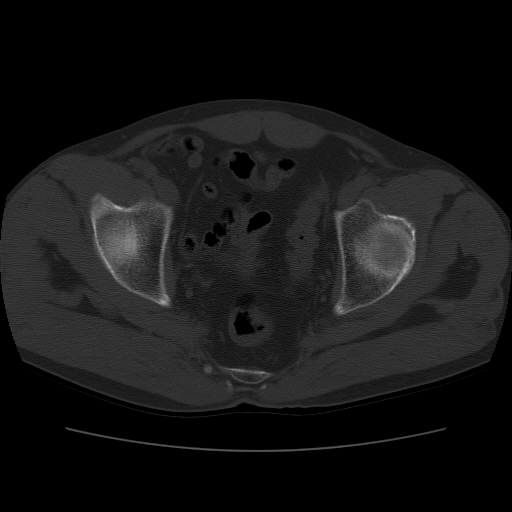

标题: CT11650:左髋病变,请会诊. [打印本页]

标题: CT11650:左髋病变,请会诊.

左髋疼痛不适近半年,局部无红肿热.无明确外伤病史.黄酒每天二餐.

考虑左侧股骨头缺血性坏死.(常期饮酒引起代谢障碍?)

左侧股骨头缺血性坏死;很典型。

“局部无红肿热.无明确外伤病史.黄酒每天二餐”。考虑左侧股骨头缺血性坏死。